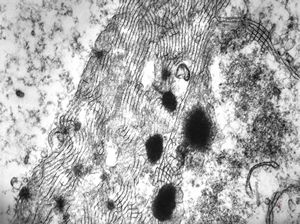

M,50y. | Pneumocystis carinii - lung